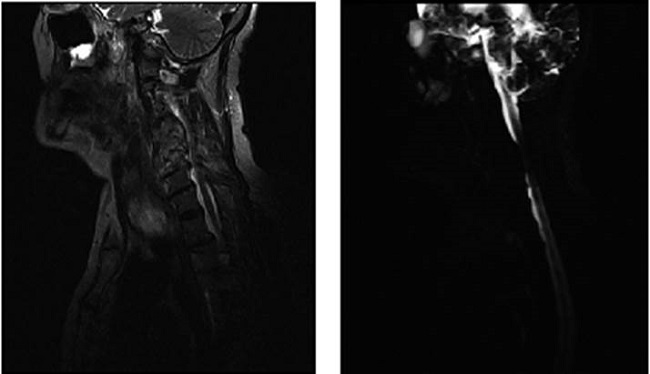

Resonancia magnética (RM) de columna cervical: Cambios degenerativos vertebrales y discales. Fusión del cuerpo vertebral C4, C5 y C6. Bloqueo vertebral entre C4 y C6 que parece secuela de una osteomielitis crónica, no se descarta imagen metastásica, aunque el muro posterior está respetado (Figura 1). Se sugiere evaluación por gammagrafía ósea.